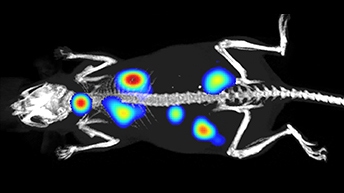

Scientists, philosophers, and artists alike are mesmerized by the brain, likening this 3 lbs of matter to a computer, a great factory, a beautiful mess, a world of unknown territory —or the most complicated object in the known universe. To even begin to understand the complex structure and function of the nervous system, including the brain, neuroscience researchers need to rely on innovative technologies, including analytical, cellular, and molecular biology, and imaging technologies.

To enable researchers to do their best research, Revvity offers a product portfolio that delivers on robust reagents and dependable instruments to help elucidate mechanisms that may better explain disease development and accelerate molecular biomarker and therapeutic discoveries.